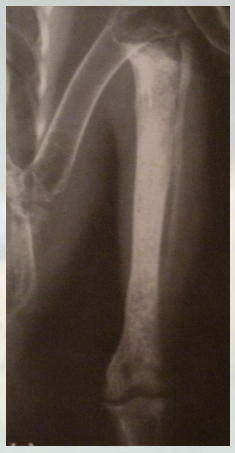

关于小型哺乳动物,它不是小型的狗。关于兔子的一个描述就是它很容易紧张,它的肺很小,但肠道非常大。兔子就是总觉得我们会把它吃掉,所以它会上有这个应激反应,即便是它的主人。兔子跟其他物种比,它的这个肺的空间非常小。

动物怎么麻醉手术环境、对象和物种差异对异宠麻醉的影响【长文预警】_https://www.jmylbn.com_新闻资讯_第38张

这是雪貂,我们可以看到它这个膈就是肺和胸腔腹腔大抵1比1的大小。

动物怎么麻醉手术环境、对象和物种差异对异宠麻醉的影响【长文预警】_https://www.jmylbn.com_新闻资讯_第39张

兔子的肺非常小,心脏在这儿。所以在麻醉中我没有办法像其他犬一样期待这个兔子有一个很深的呼吸。它通常是一个比较浅表的呼吸,常见有胃肠道的并发症,非常小的肺 是不是?它的肠道非常大。